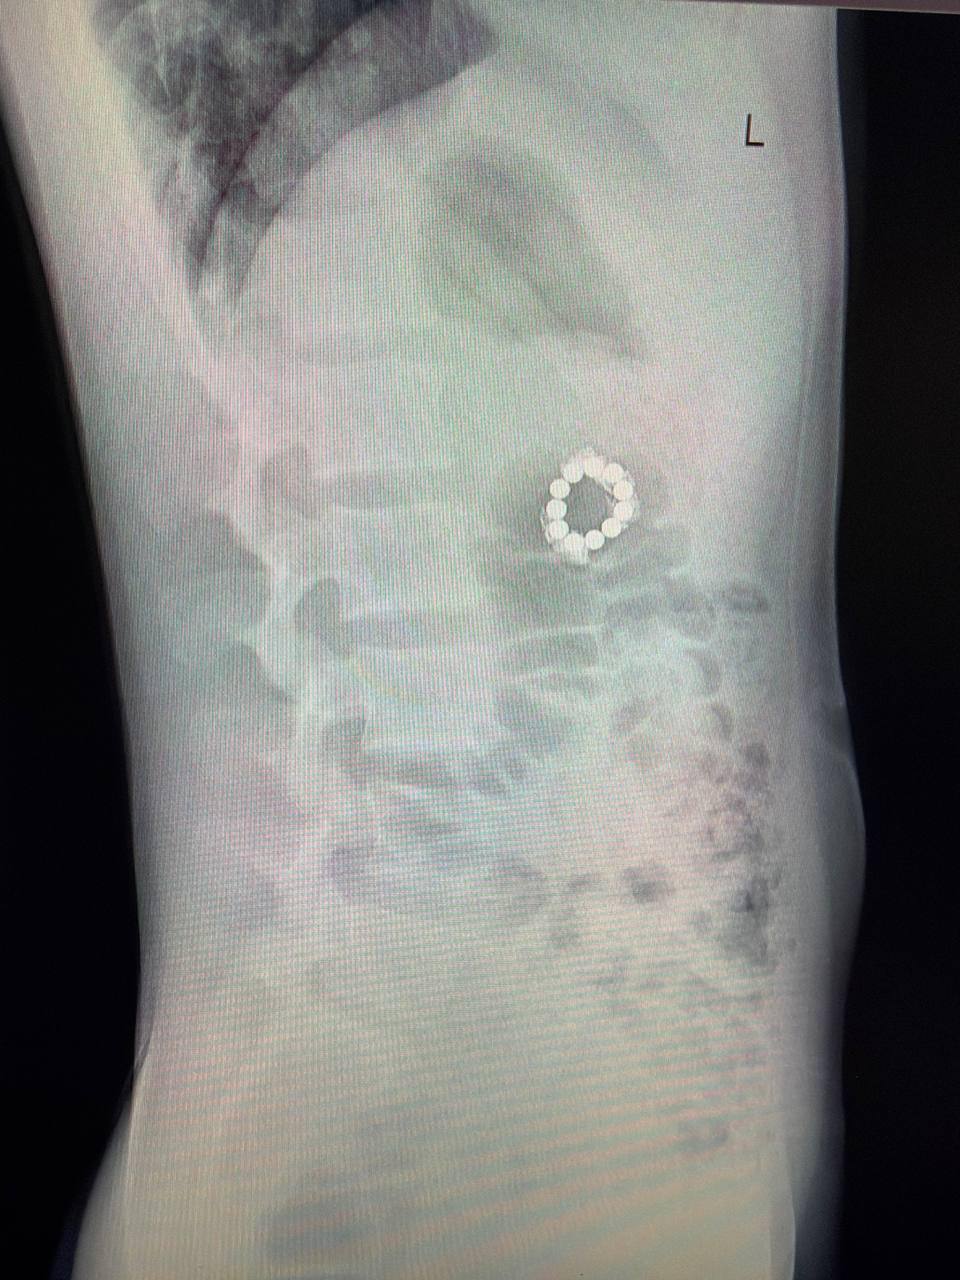

Позвоночник оказался в порядке, но на снимке заметили инородные предметы в желудочно-кишечном тракте. Выяснилось, что это магниты.

В Центре Рошаля врачи обнаружили семь магнитов в желудке и еще четыре — дальше по кишечнику. Со временем они сцепились между собой и повредили стенку желудка.